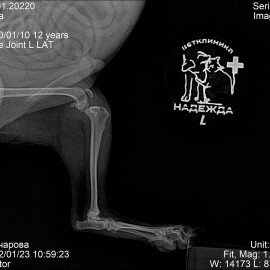

Пациент возрастом 12 лет породы йоркширский терьер по кличке Чупа.

Обратились к нам с жалобами на хромоту. На левую тазовую конечность.

После проведенных исследований был поставлен диагноз: разрыв передней крестообразной связки левого коленного сустава. Была проведена операция: TPLO.

Снимок 1 до операции.